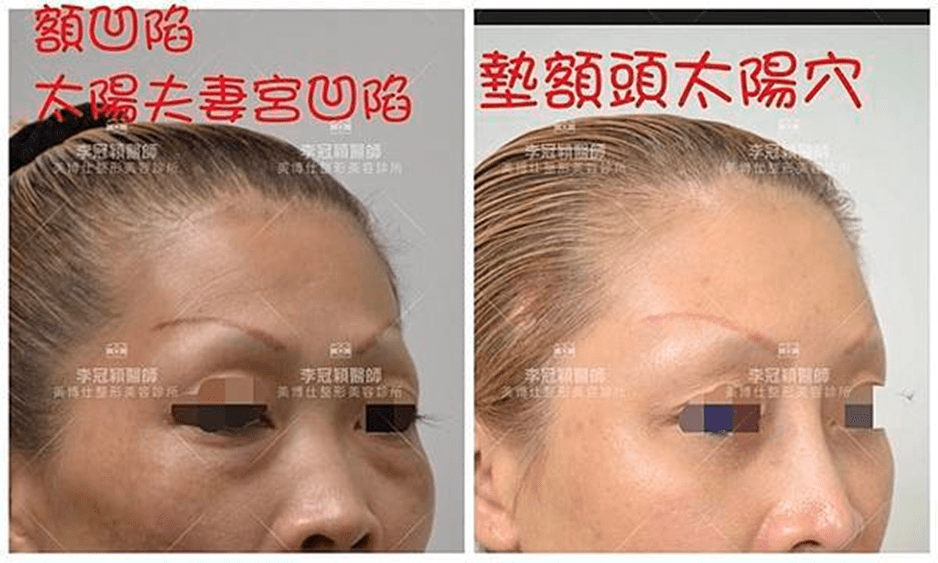

前 後(三個月)太陽穴到側額凹陷,眼尾下垂。(太陽穴不對稱往往來自顴骨大小不對稱)可以調整改善對稱性。

臉型不對稱 在太陽穴有一定落差,上圖經過太陽穴墊片矯正後,也明顯改善不對稱的視覺效果。重要的一點可以支撐眼尾下垂,改善老態眼神!(上圖)經內視鏡墊太陽穴跟提眼尾術後滿意。

下圖62歲女性:流失凹陷老態,穩定額頭和太陽穴墊片可以改善飽滿度提升年輕外觀。避免全臉填充風險副作用。